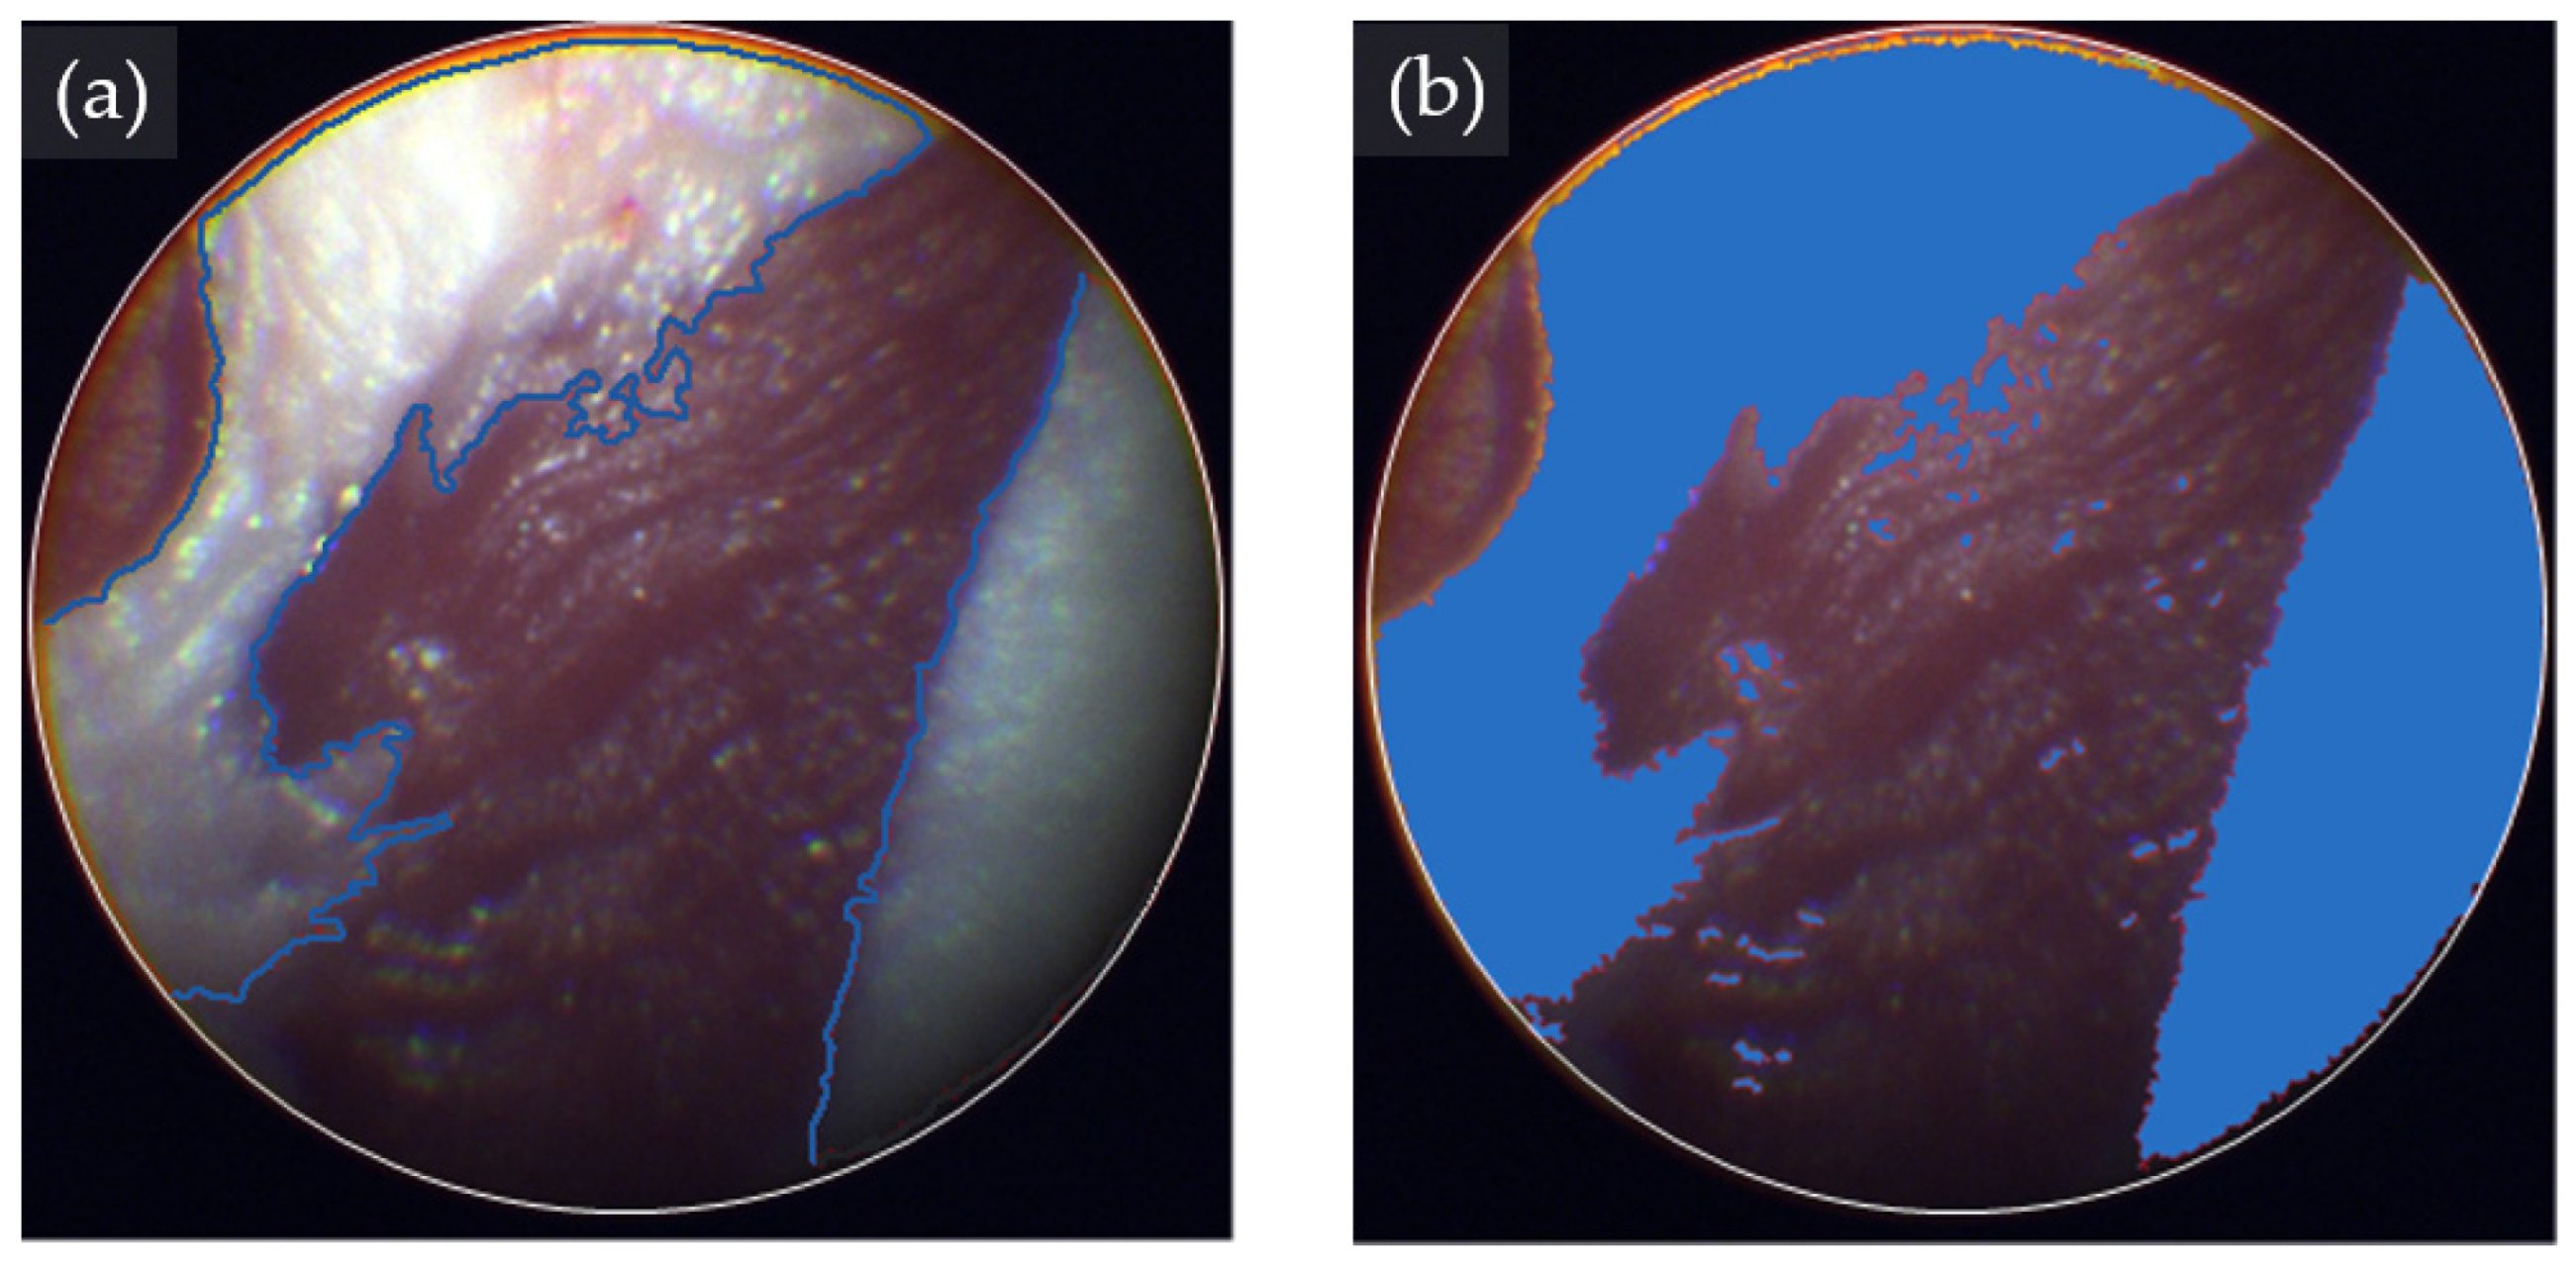

The tissue classification analysis with eHSI showed notable ability to discriminate between fat and muscle tissue (Figure 5). The classification software marked the fat tissue of the tissue phantom with a clear margin.

Figure 5.

Hyperspectral image (HSI)-based tissue classification in a tissue phantom. (a) Pseudo RGB image showing muscle and fat tissues of a tissue phantom. The margins are highlighted with blue lines. (b) HSI-based classification of fat tissues (blue-colored area) and muscle tissues using the support vector machine algorithm.

All three machine learning algorithms showed strong tissue classification performance in discriminating fat from muscle in a tissue phantom (Table 1). Regarding precision, SVM, NN, and LGBM achieved 98.3%, 97.7%, and 96.0%, respectively. Additionally, all three classification models demonstrated commendable recall values, with SVM achieving 93.4%, NN 93.8%, and LGBM 97.2%. The overall classification performance measured by the F-score, with SVM leading at 95.8%, followed closely by NN at 95.7% and LGBM at 96.6%. Notably, SVM exhibited the highest precision among the algorithms, showcasing its efficacy in discriminating fat tissue from muscle within the tissue phantom model.